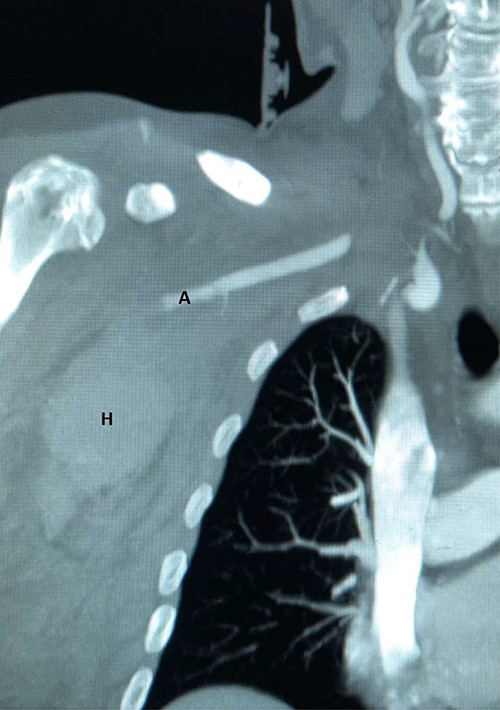

Plain radiographs of the right humerus and shoulder did not show any fracture or dislocation. A computed tomography (CT) scan with arterial phase angiography did not show and acute fracture of the cervical spine, but did reveal an abrupt cessation in flow in the right axillary artery secondary to traumatic occlusion of the vessel at the junction of segment 2 going into segment 3 with significant surrounding haematoma (Figs. 1 and 2).

3D reconstruction of CT angiography showing abrupt cessation of flow beyond segment 1 of the right axillary artery (A).

CT angiography reconstructed views demonstrating absent flow beyond segment 1 of the right axillary artery (A) with haematoma in the right axilla (H).